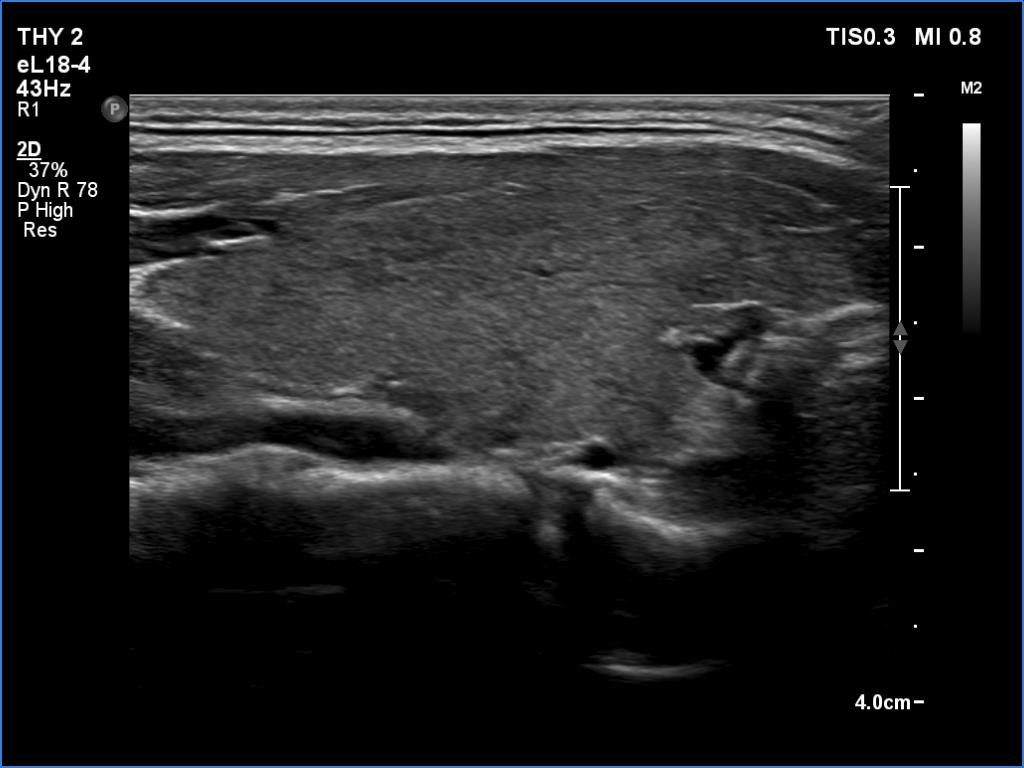

Left lobe, transverse scan

This is the usual course of Graves' disease regarding the change in echo pattern - before, during and after the activity of the autoimmune process. The only exception is the change in the size of the thyroid. In most cases, the thyroid increases during the activity of the disease, then returns to normal. However, in this patient the age counts: at the first examination, the patient was only 15-year-old.

- There are two situations in Graves 'disease where circulation is increased. At the stage of disease activity and when hypothyroidism is observed with medication. In the former case, the blood flow is almost always increased, in the latter it can be decreased and increased.